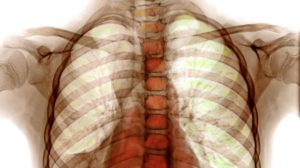

| Диагностика | Рентгенография грудной клетки, КТ легких, бронхоскопия, исследование функции внешнего дыхания, иммунологические тесты, потовый тест, генетические исследования. | Направлена на выявление основной причины, а не только подтверждение воспаления. |

Обследование может включать бронхоскопию, КТ легких, анализ пота и пробу Манту. Второе важное правило в борьбе с повторной пневмонией – новый курс не должен дублировать предыдущее лечение. Для детей обычно назначают препараты последних поколений, которые оказывают минимальное воздействие на растущий организм. Например, это могут быть таблетки из группы цефалоспоринов и фторхинолонов.

Клинически повторное заболевание, как правило, проявляется значительно сильнее, чем первичный случай. Однако на начальных этапах его трудно распознать, поскольку пациент может считать, что вновь появившиеся симптомы являются следствием ранее перенесенной болезни. Рентгенологическое обследование легких играет ключевую роль в определении характера протекания заболевания.

- Рентгенологическое исследование демонстрирует увеличение пораженной области или изменение характера заболевания на очаговое, что подразумевает наличие множественных поражений.

Установить более точный диагноз с определением степени поражения легкого (также, как распознать бронхит у ребенка и любое другое бронхолегочное заболевание) можно с помощью рентгенографии.

В медицинских источниках можно встретить различные определения повторной пневмонии. В педиатрической практике это заболевание характеризуется как два или более случая в течение одного календарного года, либо более трех эпизодов за неограниченный период времени. При этом рецидив подтверждается рентгенографическими данными, которые показывают освобождение легочной ткани при наличии инфильтрации.